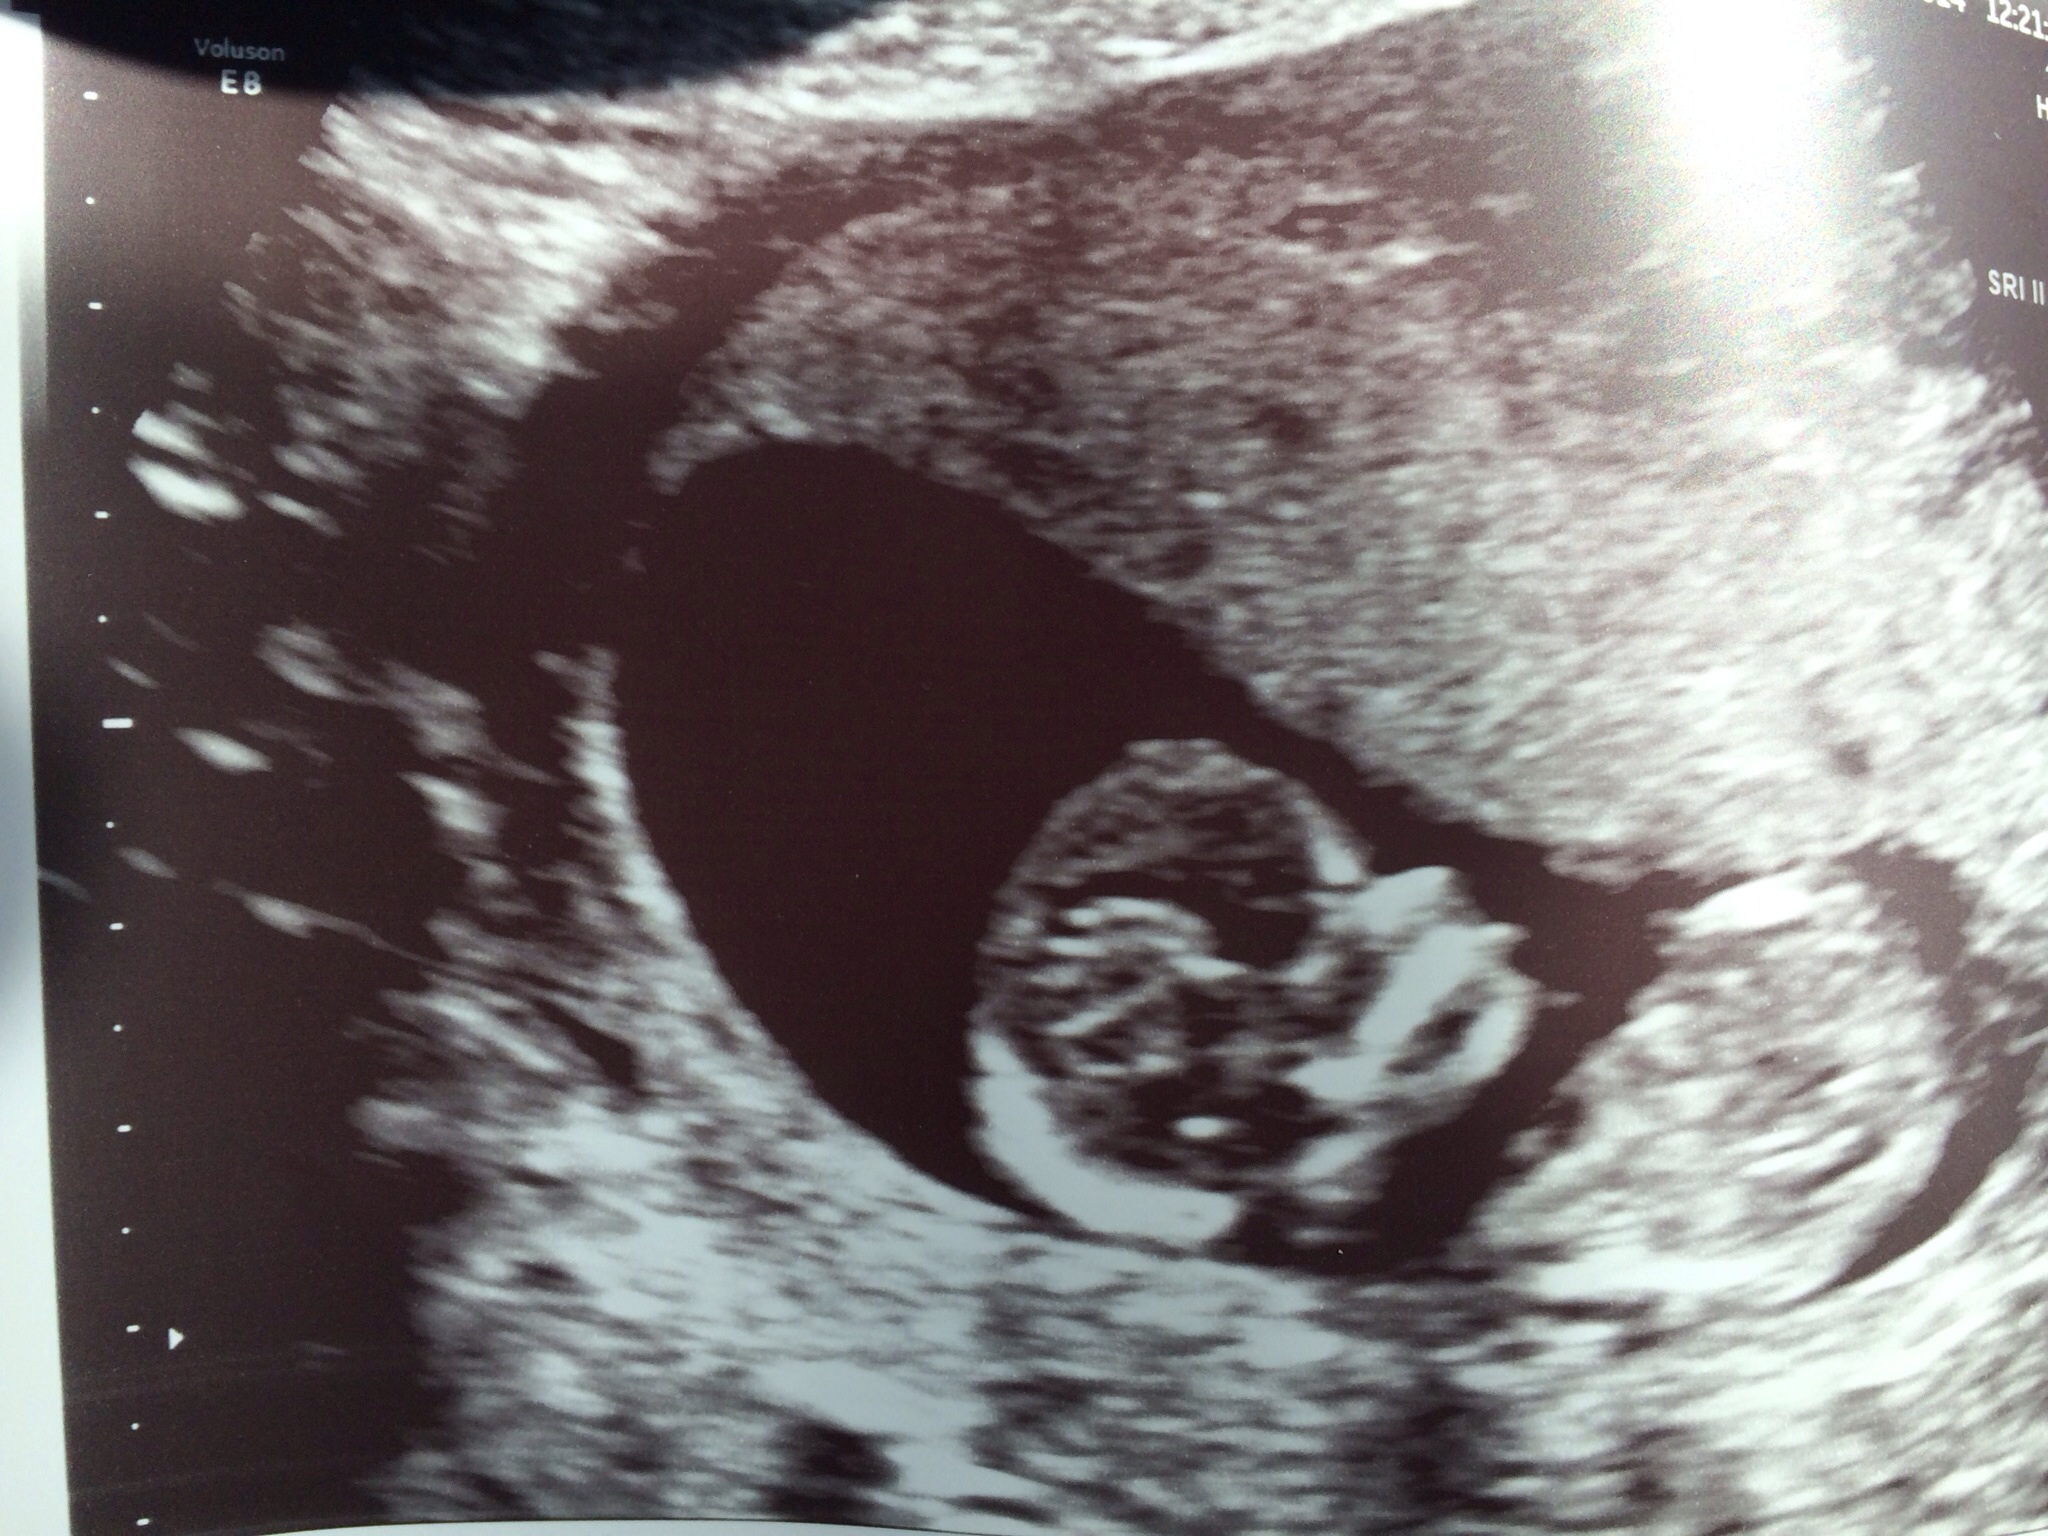

Found out today I am indeed having a girl! Never in a million years would I think I'd be this lucky!!!!Attachment 19448

Woot woot! I won't blow up this board too...haha. congrats again!!

That's great! Congratulations!! :). Enjoy. Must be an amazingly feeling.